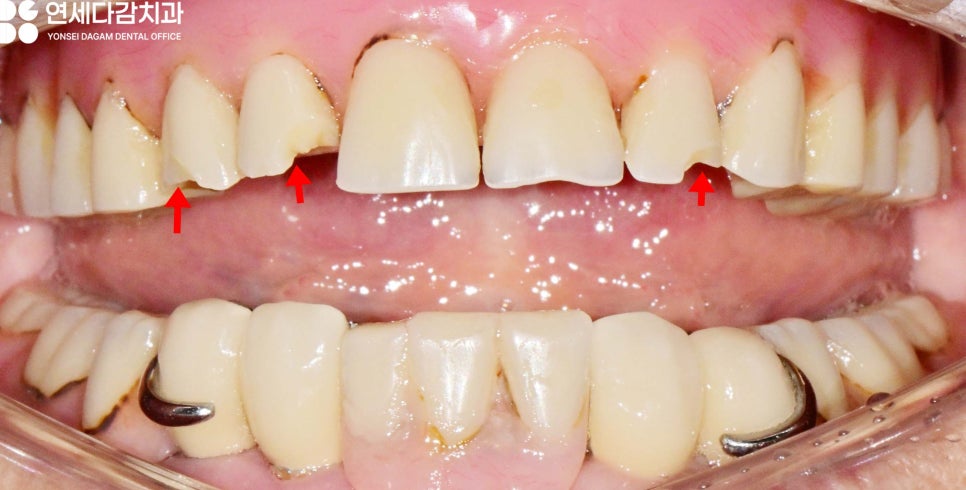

예를 들어 로케이터 타입의 오버덴쳐,

흔히 똑딱이 틀니라고 불리는 것을

사용 중이라면,

오버덴쳐는 임플란트와 연결되는

특수한 구조를 가지고 있으므로

수리 과정에서 이 부분에는 문제가 없는지

확인하는 과정이 필요합니다.

따라서 어떤 유형의 틀니인지 정확히 알아야

손상 부위와 원인을 파악한 후

적절한 수리 방법을 결정할 수 있답니다.